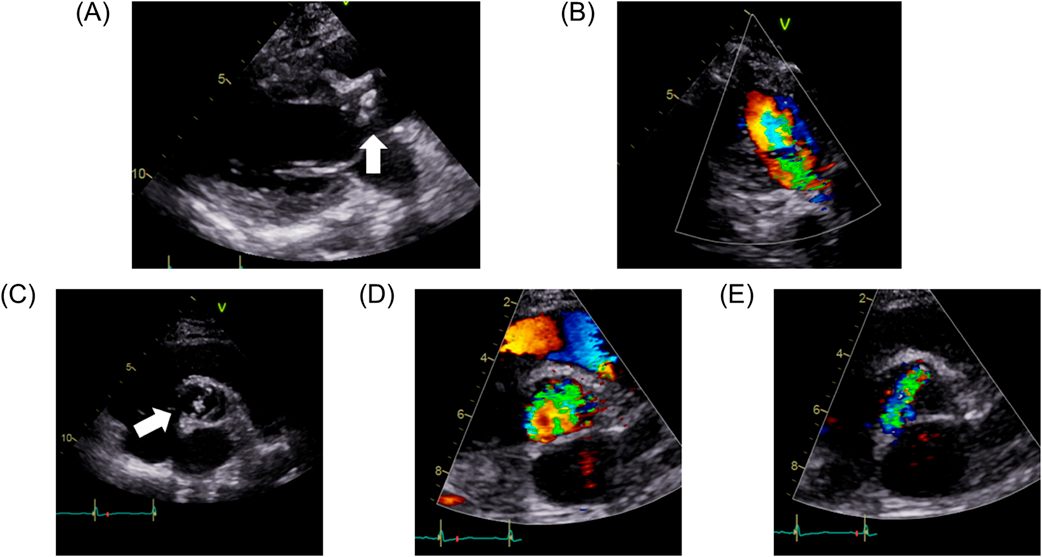

Her postoperative course was uneventful. She was extubated on the postoperative day 2, discharged from the intensive care unit on the day 5, and discharged from the hospital on the day 11. Postoperative echocardiography showed that peak velocity and peak pressure gradient had decreased to 2.30 m/s and 21.2 mmHg, respectively. On contrast-enhanced CT, diameters of the aortic annulus, the sinus of Valsalva, and the sino-tubular junction had been enlarged to 25.2 mm, 28.3 mm×25.9 mm, and 22.4 mm×24.6 mm, respectively. The distances between the bioprosthetic valve leaflets and the right and the left coronary ostia were 4.0 mm and 4.7 mm, respectively. Fig. 3 shows the sinus of Valsalva on contrast-enhanced CT before and after the surgery.

Fig. 3 Contrast-enhanced computed tomography before and after surgery

(A) The Valsalva sinus before surgery measured 22.9 mm×22.2 mm. (B) After surgery, it measured 28.3 mm×25.9 mm. (C) The distances between the bioprosthetic valve leaflets and the right and the left coronary arterial ostia were 4.0 mm and 4.7 mm, respectively.

As for the size and the type of a bioprosthetic valve, we used 21 mm INSPIRIS RESILIA valve®. One can argue that a larger-sized valve could have been selected and would be more advantageous for future TAVR. However, a larger-sized valve can lead to smaller distances between the bioprosthetic valve leaflets and the coronary arterial ostia, increasing the risk of coronary orificial obstruction after valve-in-valve TAVR. In our case, the valve-to-coronary arterial distances were 4.0 mm for the right coronary ostium and 4.7 mm for the left coronary ostium on postoperative CT. This result indicates that our selection of the valve size was reasonable, considering the fact that the valve-to-coronary arterial distance less than 4.0 mm has been reported to be a risk for coronary orificial obstruction.5) INSPIRIS RESILIA valve is designed to dilate its valve annulus at TAVR. The annulus-dilatable design of INSPIRIS was demonstrated in the previous report from our department.6) Based on the patient’s body size, the 21 mm INSPIRIS RESILIA valve could allow TAVR twice eventually.